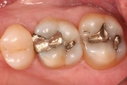

Diş ekimi, kaybedilen dişlerin yerine yapay dişlerin yerleştirilmesi işlemidir. Bu işlem, hem estetik hem de fonksiyonel açıdan birçok avantaj sunmaktadır. Diş ekimi, günümüzde diş hekimliği alanında en yaygın kullanılan yöntemlerden biri haline gelmiştir. Bu makalede, diş ekiminin faydaları detaylı bir şekilde ele alınacaktır. Diş Ekimi Nedir?Diş ekimi, kaybedilen dişlerin yerine cerrahi bir işlemle titanyum veya benzeri malzemelerden yapılan yapay diş köklerinin yerleştirilmesini içeren bir tedavi yöntemidir. Bu işlem, diş kaybının neden olduğu estetik kaygıları gidermenin yanı sıra, çiğneme fonksiyonunu da yeniden kazandırmaktadır. Diş Ekiminin Estetik FaydalarıDiş ekimi, hastaların gülümseme estetiğini önemli ölçüde iyileştirmektedir. Aşağıdaki avantajlar estetik açıdan dikkate değerdir:

Diş Ekiminin Fonksiyonel FaydalarıDiş ekiminin fonksiyonel avantajları da oldukça önemlidir. Bu avantajlar şunlardır:

Diş Ekiminin Sağlığa FaydalarıDiş ekimi, sadece estetik ve fonksiyonel avantajlar sunmakla kalmaz, aynı zamanda sağlık açısından da faydalar sağlar:

Diş Ekimi SüreciDiş ekimi süreci, genellikle birkaç aşamadan oluşur: